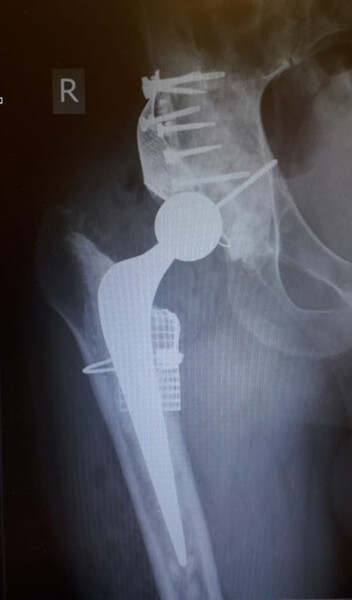

研究人員認為,借助3D打印技術,整形外科醫(yī)生將能夠縮短手術時間,同時改善臨床效果,如減少術后骨折的質量,髖關節(jié)功能和并發(fā)癥發(fā)生率。實際上,以前3D打印已在各種類型的髖關節(jié)手術中獲得成功的應用。在2019年末,LOGEEKs Medical Systems(MS)透露,其3D打印植入物已與髖關節(jié)植骨結合用于髖關節(jié)的重建修復手術中。在此之前的一年,佛羅里達的外科醫(yī)生還使用ConforMIS(一家位于馬薩諸塞州的醫(yī)療技術公司)的3D打印植入物進行了髖關節(jié)置換手術。手術結果,顯示了3D打印的植入物

手術結果,顯示了3D打印的植入物。圖片來自LOGEEKs。